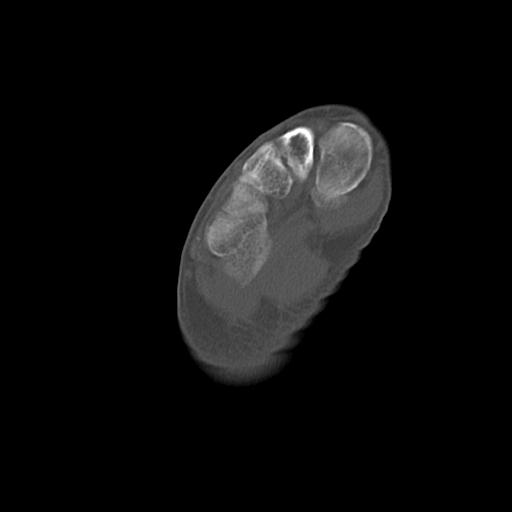

110286 2/17 股関節 2R 74歳女性 右人工骨頭

82084 1/14 1/20 股関節 2R 78歳男性 右人工骨頭

102811 1/13 股関節 2R 1/19 2R 80歳女性 右DHS